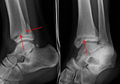

Bimalleolar fracture and right ankle dislocation on X-ray (anteroposterior). Both the end of the fibula (1) and the tibia (2) are broken and the malleolar fragments (arrow: medial malleolus, arrowhead: lateral malleolus) are displaced. | |

On X-rays, there can be a fracture of the medial malleolus, the lateral malleolus, or of the anterior/posterior margin of the distal tibia. The posterior margin (known as the posterior malleolus) is much more frequently injured than the anterior aspect of the distal tibia. If both the lateral and medial malleoli are broken, this is called a bimalleolar fracture (some of them are called Pott's fractures). If the posterior malleolus is also fractured, this is called a trimalleolar fracture.